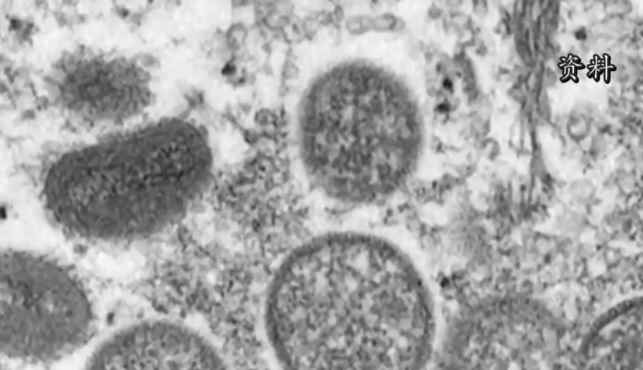

世衛組織:不必擔心猴痘會引發全球大流行

猴痘是一種病毒性人畜共患病,猴痘病毒可通過密切接觸由動物傳染給人,雖不易發生人際傳播,但與感染者密切接觸也可能感染。人感染猴痘的初期症狀包括發燒、頭痛、肌肉酸痛、背痛、淋巴結腫大等,之後可發展為面部和身體大範圍皮疹。多數感染者會在幾周內康復,但也有感染者病情嚴重。(完)